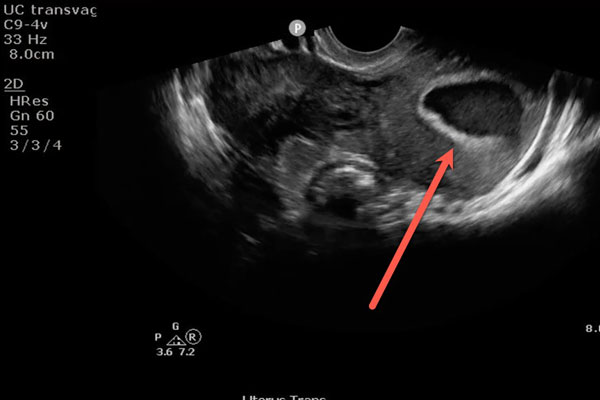

اما در بارداری های پوچ اگرچه ممکن است نتیجه اول آزمایش بارداری مثبت شود، اما با گذشت زمان و با تشکیل نشدن جنین عدد بتا مطابق سطح انتظار بالا نخواهد رفت و به مرور افت پیدا می کند تا در نهایت بارداری خاتمه پیدا می کند. به همین دلیل گفته می شود تغییرات عدد بتا در بارداری های پوچ جزو علائم هشدار دهنده این موضوع است. پزشکان معتقدند تنها معیار درست برای تشخیص بارداری پوچ افزایش عدد بتا نیست و باید به موارد دیگر نیز توجه کرد. به همین دلیل توصیه می کنند جهت تشخیص بارداری های پوچ شاخص تغییرات عدد بتا را مد نظر قرار ندهند و منتظر باشند در هفته مناسب با انجام سونوگرافی جواب دقیق آزمایش را دریافت کنند.